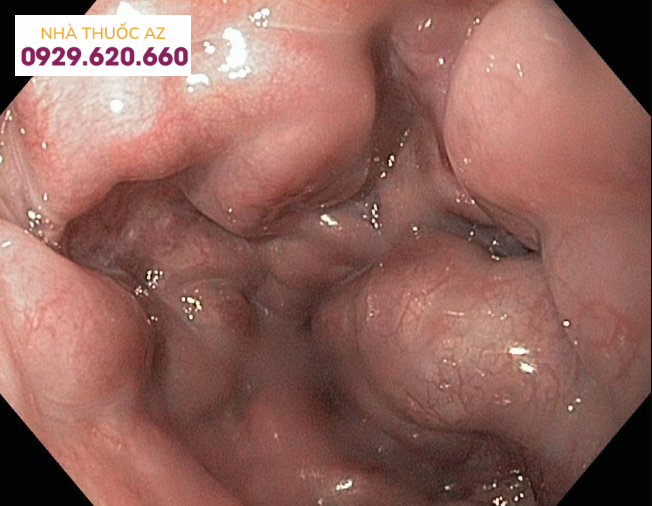

Chứng ợ nóng: LES đóng không hoàn toàn cho phép các chất chứa trong dạ dày có tính axit dự phòng (trào ngược) vào thực quản. Trào ngược có thể gây ợ nóng, ho hoặc khàn giọng, hoặc không có triệu chứng nào cả.Bệnh trào ngược dạ dày thực quản (GERD): Khi trào ngược xảy ra thường xuyên hoặc gây khó chịu, nó được gọi là bệnh trào ngược dạ dày thực quản (GERD).Viêm thực quản: có thể là do kích ứng (như do trào ngược hoặc xạ trị) hoặc nhiễm trùng.Thực quản Barrett: Trào ngược thường xuyên của axit dạ dày kích thích thực quản, có thể làm cho phần dưới thay đổi cấu trúc của nó. Trong một số trường hợp, thực quản Barrett tiến triển thành ung thư thực quản.Loét thực quản: loét xảy ra ở một khu vực của niêm mạc thực quản. Điều này thường được gây ra bởi trào ngược mãn tính.Co thắt thực quản: Thu hẹp thực quản. Kích thích mãn tính từ trào ngược là nguyên nhân thông thường của hẹp thực quản.Achalasia: Một bệnh hiếm gặp trong đó cơ thắt thực quản dưới không họa động đúng cách. Khó nuốt và nôn ra thức ăn là triệu chứng của tình trạng này.Ung thư thực quản: Mặc dù bệnh vô cùng nghiêm trọng, tuy nhiên ung thư thực quản không xảy ra phổ biến. Các yếu tố nguy cơ ung thư thực quản bao gồm hút thuốc, uống nhiều rượu và trào ngược mãn tính.Rách Mallory- Weiss: Nôn lại tạo ra vết rách ở niêm mạc thực quản. Thực quản chảy máu vào dạ dày, thường kèm theo nôn ra máu.Giãn tĩnh mạch thực quản: Ở những người bị xơ gan, tĩnh mạch trong thực quản có thể bị căng và phình ra được gọi là giãn tĩnh mạch, những tĩnh mạch này dễ bị chảy máu đe dọa tính mạng.Vòng thực quản (vòng Schatzki): Một sự tích lũy mô lành tính xảy ra phổ biến trong một vòng quanh đầu thấp của thực quản. Nhẫn của Schatzki thường không gây ra triệu chứng, nhưng có thể gây khó nuốt.Mạng thực quản: Sự tích tụ mô (tương tự như vòng thực quản) thường xảy ra ở thực quản trên. Giống như nhẫn, mạng thực quản thường không gây ra triệu chứng.Hội chứng Plummer-Vinson: Một tình trạng bao gồm thiếu máu thiếu sắt mãn tính, mạng lưới thực quản và khó nuốt. Bổ sung sắt và giãn nở của thực quản là phương pháp điều trị.

Tĩnh mạch trong thực quản có thể bị căng và phình ra